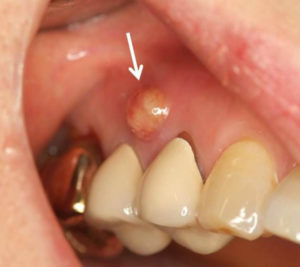

フィステル(ろう孔)、サイナストラクトとも呼ばれている。